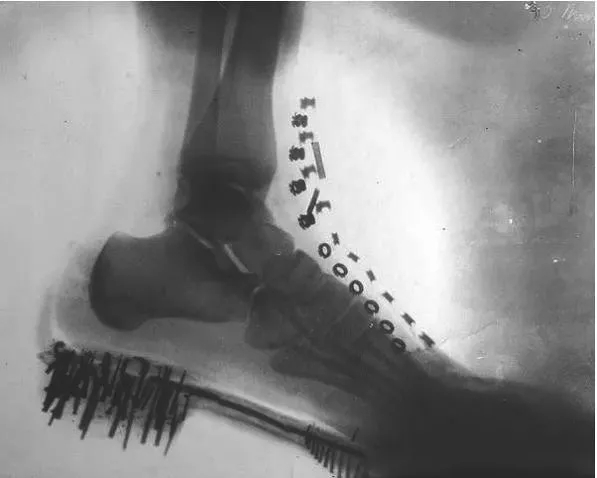

特斯拉用自己的身体试验X射线

这是他拍摄的脚部影像图